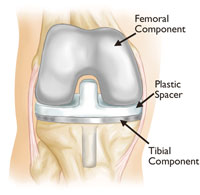

- Minimally invasive bone preserving Arthroplasty e.g. UKR (half a knee replacement)

The last option is a Total Knee Replacement. (Replacement of all 3 compartments – inside, outside and the front of the knee)

A person in mid 60’s will be 75-80 years of age before his/her knee wears out. If you have followed my previous post – I have to resect some of your bone (not much with navigation technique) to replace it with metal and plastic.

There are 2 issues here-

- I have taken some of your bone away

- I have put plastic (soft) material between chrome cobalt and titanium.

So as you move the knee and since you are young, you will move it a lot more than a 65-70-year-old. As you move the plastic undergoes a wear process and releases very minute plastic particles in the knee joint. These particles have nowhere to go. However, the body detects that there is something foreign in the knee joint floating around. It sends its soldiers, the white cells to fight this foreign enemy. Usually, this foreign enemy is either virus or bacteria and the usually this war is won by the body.

This time the enemy is non-biological. The white cells in an attempt to kill the plastic will ingest (engulf) it but are unable to kill it and it the process the white cell releases all the toxic enzymes as it dies into the knee joint. These enzymes really have no effect on the metal or the plastic but it now starts to dissolve the bone behind the knee replacement and so the knee comes loose and the patient starts developing pain again.